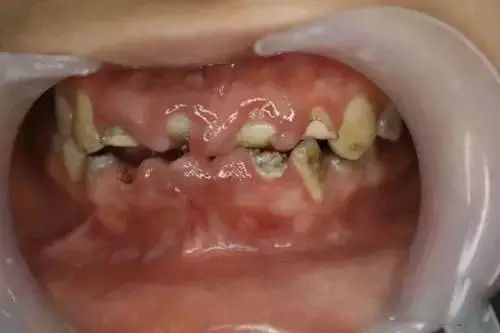

喺最極端嘅情況底下

佢甚至可以毀掉你整口牙齒

如下圖咁樣(前方再次高能預警):

呢個係一個嚟自美國嘅真實案例。呢位好鍾意飲可樂嘅男仔年紀還青青就失咗所有嘅牙齒

喺醫學界,呢個情況叫做“酸蝕症”,簡單嚟講就係牙齒長期同酸性物質接觸導致嘅牙齒硬組織溶解失去。

尤其重要嘅係:對於兒童嚟講,飲料嘅危害更大!因為剛萌出的牙齒尚未鈣化完全,更容易俾酸性物質溶解侵蝕。再支邊,小朋友仲特別鍾意飲甜甜嘅飲料,同時又未學會正確刷牙技巧。